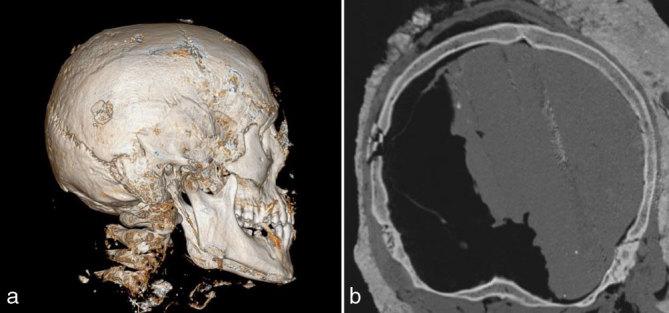

Assessment of head gunshot wounds by means of post-mortem computed tomography in exhumed anonymous cadaver.

Autopsy of corpses with advanced post-mortem changes is the most challenging aspect of medico-legal activities. In many cases, owing to soft tissue decomposition, making a final diagnosis as to the mechanism and cause of death is very difficult, and sometimes impossible (Carcione P, Argo G, Pincone D, Zgo S, Scopelliti L, Sortino C, Procaccianti P. Role of MCT vitropsy in evaluation of burned bodies and its comparison with traditional autopsy. Poster No.: C-1156, ECR 2014, Scientific exhibit). In such cases, the diagnostic process can be supported by post-mortem CT imaging. Post-mortem multislice CT imaging used in the field of forensic medicine is widely reported to be a good method for visualizing injuries and natural pathologies; however, only a limited number of forensic departments use this method in everyday practice. This method enables accurate assessment of bony injuries (fracture type, degree of bone displacement); has the ability to detect radiopaque foreign bodies, most frequently fragments of bullets; and in some cases enables soft tissue delineation (Hardy K. CT autopsy. 2008; 9: 20. Available from: http://www.radiologytoday.net/archive/rt01282008p20.shtml). In cadavers with advanced post-mortem changes, it is extremely difficult to retrieve the whole bullet or its parts. Owing to decomposition and reduced cohesion of the tissues, standard autopsy preparation techniques are impossible to perform. Post-mortem changes may also cause displacement of the bullet within the body in the long term, as well as at the time of transport following exhumation (Maiese A, Gitto L, De Matteis A, Panebianco V, Bolino G. Post mortem computed tomography: useful or unnecessary in gunshot wounds deaths? Two case reports. 2014; 16: 357-63). It is therefore important to perform post-mortem CT imaging directly after extraction of corpses in a similar position to how the dead body was exhumed. Interpretation of the images requires cooperation of forensic medicine specialists and radiologists to correlate radiological findings with autopsy.